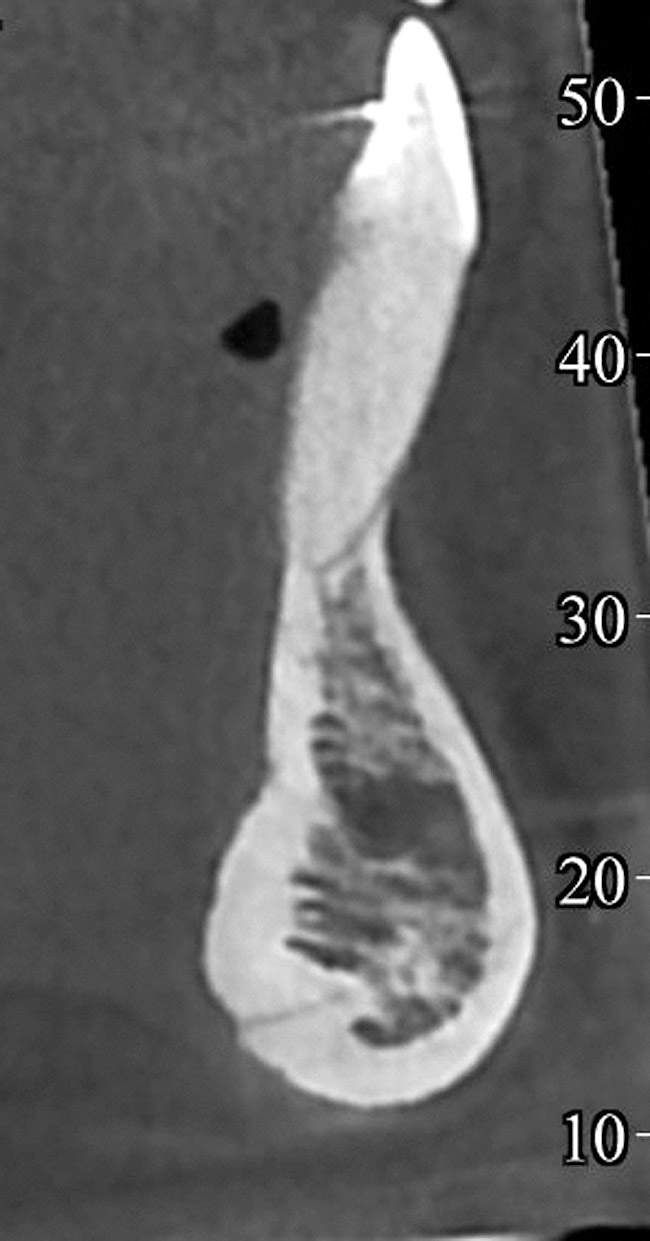

Fig 18. CBCT sagittal view shows no bone on the labial aspect and 2.5 mm bone thickness on the lingual aspect.

Figure 18

When teeth with GR present with an increased labial root inclination and prominence, orthodontic correction of tooth position should be then considered. The decision about whether orthodontic treatment is possible depends on the thickness of the bone lingual to the affected root. The only modality to accurately assess the labio-lingual thickness of the alveolar bone is cone-beam computerized tomography (CBCT) imaging. Studies that compared measurements on cadavers and CBCT showed that CBCT measurements are an accurate representation of the clinical bone thickness.31-33

Based on these data, a minimum of 2.5 mm of lingual alveolar bone thickness, measured on CBCT views at 8 mm apical to the CEJ, is recommended for orthodontic tooth repositioning of a labially displaced root.

A 19-year-old female complaining of gingival recession in the lower right central incisor presented to the authors’ clinic 5 years after completion of orthodontic treatment. The clinical evaluation showed Miller Class II GR accompanied by gingival inflammation (Figure 14). Two years later, despite conservative periodontal treatment, the GR had worsened (Figure 15). The occlusal view shows the presence of a fixed lingual retainer and a significant labial displacement of the root of the affected incisor (Figure 16 and Figure 17). At this stage, orthodontic treatment was considered. The patient was referred for CBCT, which showed no labial bone coverage of the root but 2.5 mm lingual bone thickness at 8 mm distance from the CEJ (Figure 18). After 6 months of orthodontic treatment with fixed appliances (Figure 19), the B-L inclination of the affected tooth was corrected (Figure 20). The frontal clinical view shows narrowing of the GR (Figure 21). Surgical coverage of the exposed root was subsequently performed by connective tissue graft (Figure 22). A long-term stable and esthetic result was achieved (Figure 23).